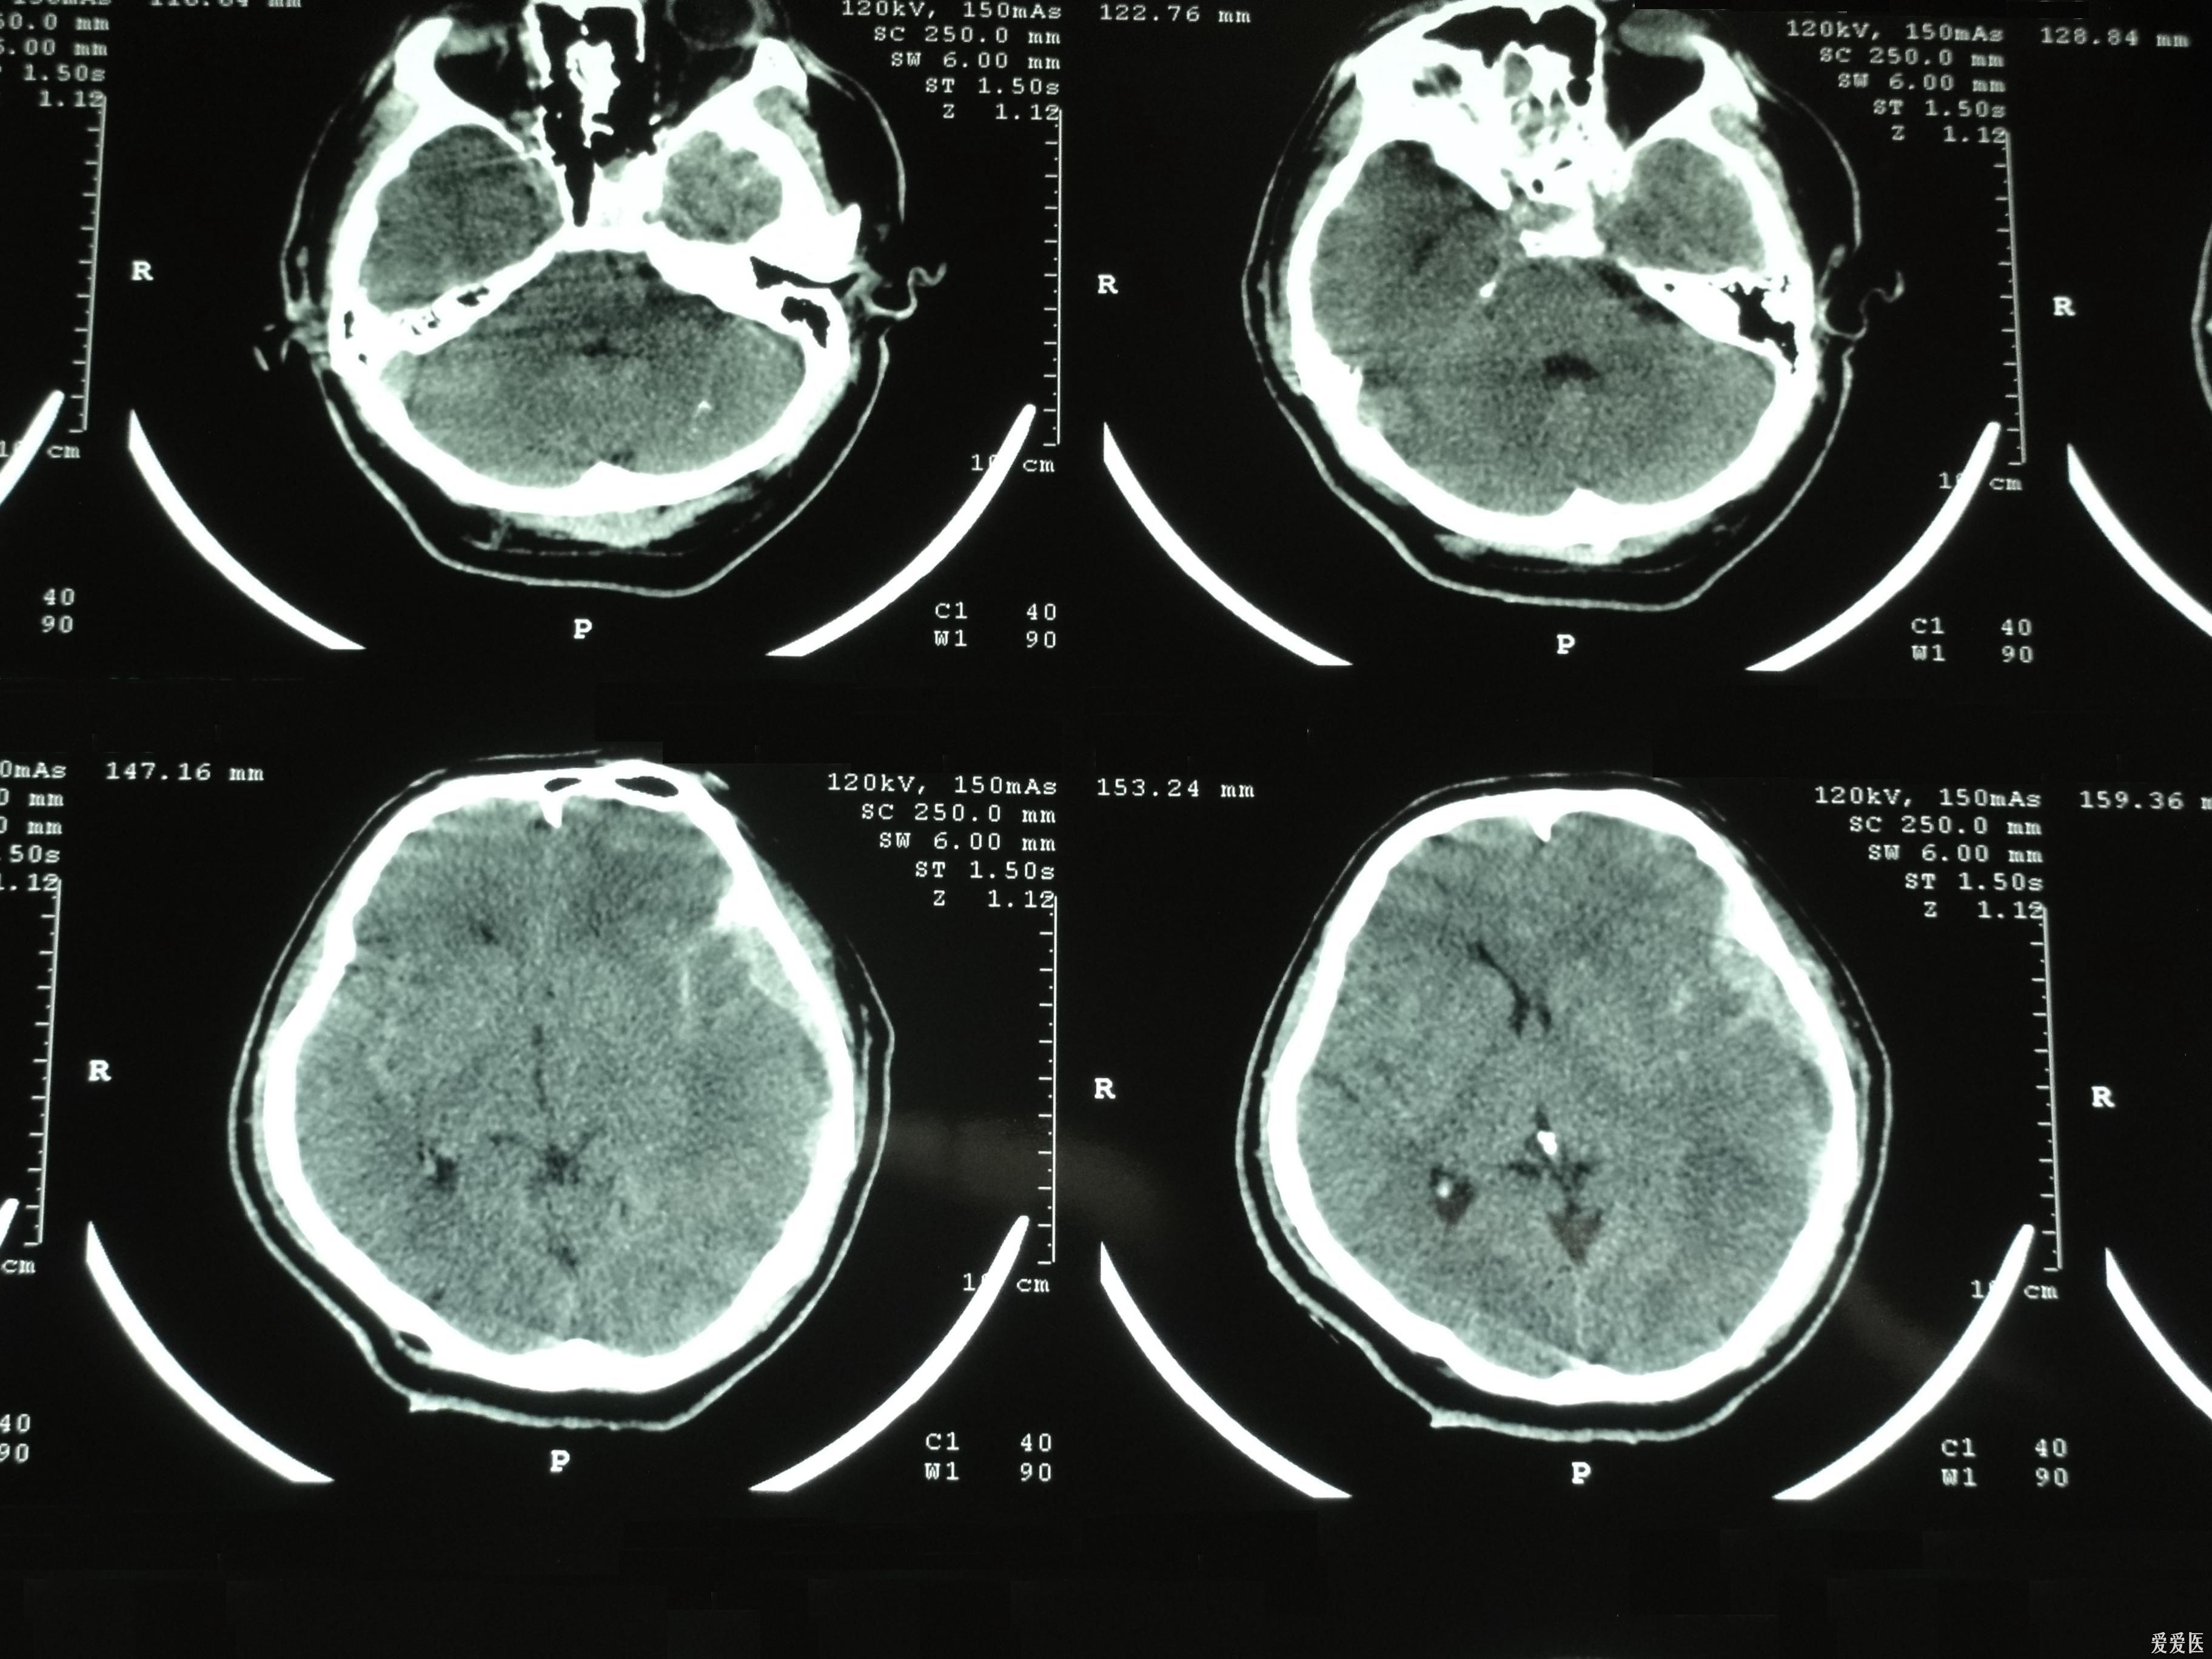

硬膜外血肿

图片尺寸3264x2448